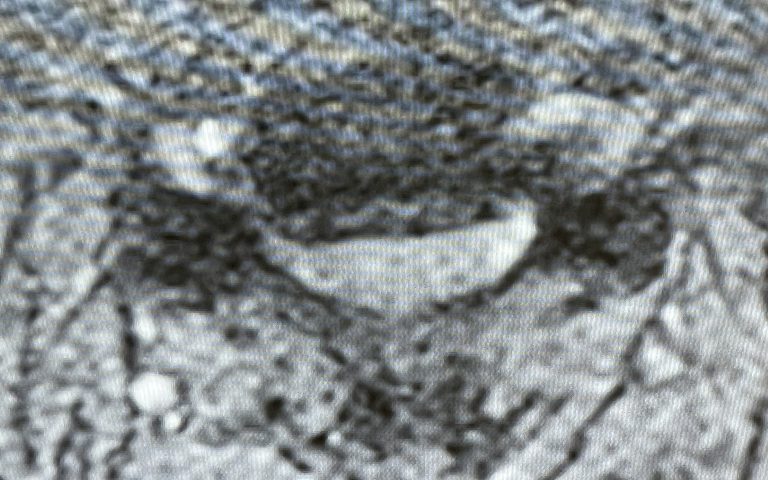

Here is the case of a 51 year-old female who had a ten year history of severe neck pain with severe right arm pain, numbness, and weakness. She weighed over 300 pounds. She had failed all means of conservative management including medicines, physical therapy, chiropractic care, and epidurals. MRI demonstrated a reverse of the normal curvature of the cervical spine with large disc osteophyte complexes compressing the spinal cord (Fig 1). The C4-5 disc osteophyte was larger causing severe anterior compression of the spinal cord, worse on the right side (Fig 2). This correlated with the patient’s clinical findings. Therefore surgery was recommended. Patient underwent an anterior cervical discectomy and fusion with a plate from C4-C6. We were able to get her into a good position. Although there was a very deep exposure through the fat layer, it was not too bad to expose the face of the spine (Fig 3). Because there is less muscle, tissue planes open up actually easier sometimes particularly in women because of a relative decrease in muscle mass. The same goes for exposure of the lumbar spine. The majority of “herniated discs” in the cervical spine are actually bony protrusions we call osteophytes. After you clear away all the other cartilage that is the soft part of the disc, the way to get rid of that C4-5 osteophyte which acts like a sheet of bone at the posterior aspect of the disc space, is to drill it down to a fine shell and remove it with a special tool. This tool is called a Kerrison and has a very thin footplate that allows a plane between the osteophyte and dura which is being compressed and bites away this bone. The patient had good relief of her symptoms postoperatively.

Fig 3: Intraoperative photo showing a deep exposure with deep retractors to access the anterior cervical spine